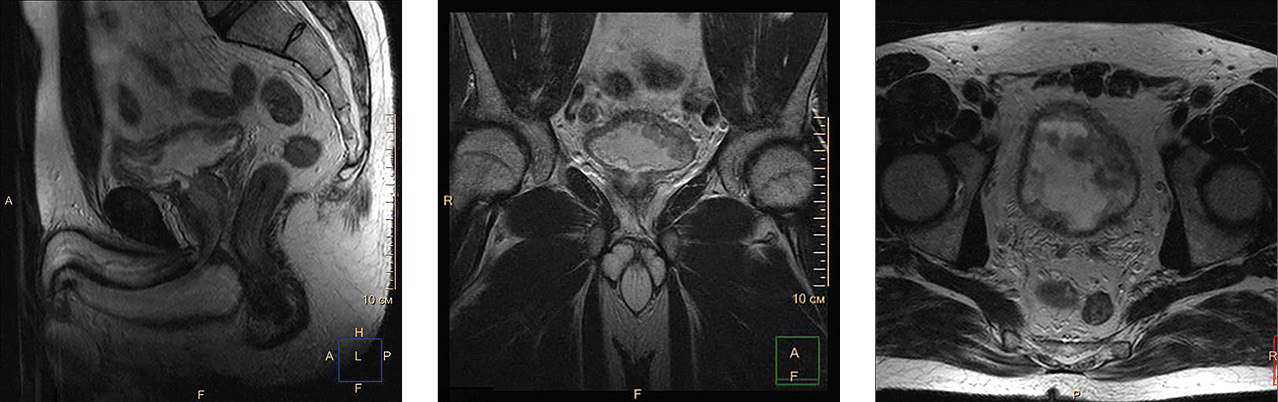

Через 4 недели после пенэктомии пациенту назначена лекарственная противоопухолевая химиотерапия. Однако уже через 2 месяца после ее начала обнаружены отдаленные метастазы в паренхиму легких и печень, в кости таза и лимфатические узлы паховой области (рис. 3). Назначена 2-я линия лекарственной противоопухолевой терапии. Несмотря на проводимую терапию, 12 мая 2021 г. (через 22 месяца после ЦЭ и через 5 месяцев после пенэктомии) зафиксирована смерть пациента.

Рис. 3. Компьютерная томограмма грудной клетки, брюшной полости и малого таза. Дальнейшее прогрессирование заболевания: метастазы в легочную ткань (сплошные стрелки), паренхиму печени (пунктирная стрелка), лонные кости и паховые лимфатические узлы (открытые стрелки)